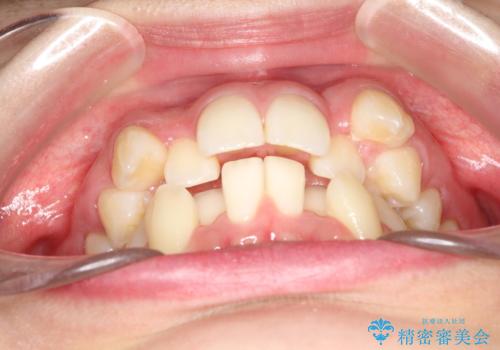

- 八重歯と前歯のガタガタを主訴に来院されました。

目立たない装置をご希望でしたので、上下左右の歯を1本ずつ抜歯してハーフリンガルでの矯正を行いました。